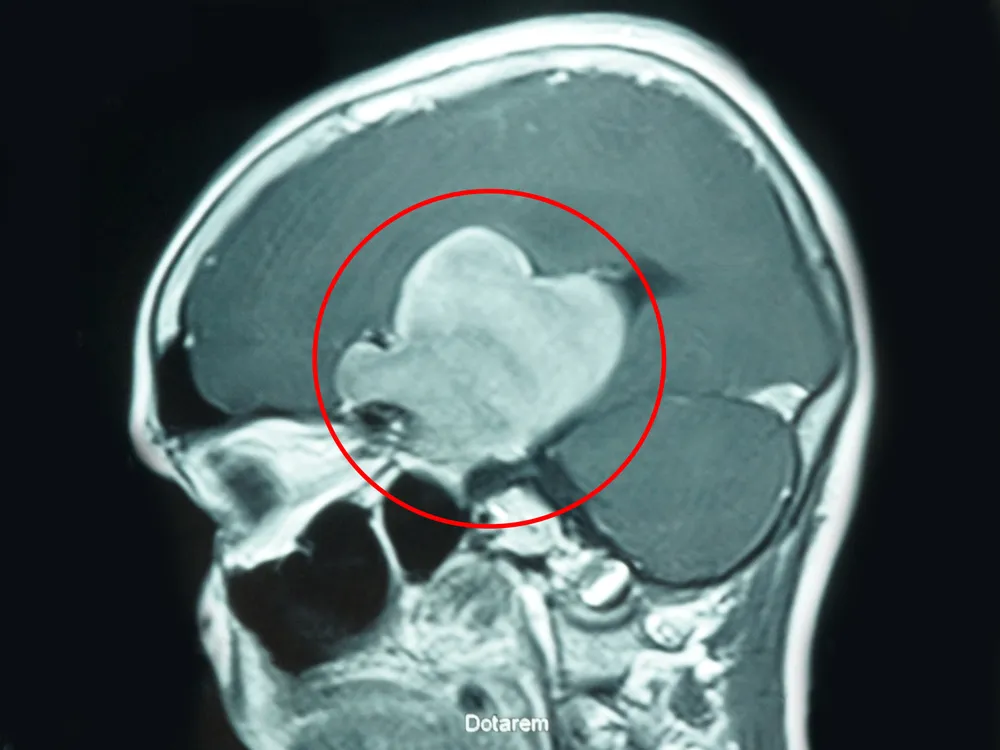

Bóc tách thành công khối u não khổng lồ cứu sống bệnh nhân ảnh 1 Khối u kích thước rất lớn chiếm gần như hết bán cầu não bên phải cho bệnh nhân

Tại đây, sau thăm khám và kiểm tra lâm sàng, các bác sĩ chuyên khoa Ngoại Thần Kinh chẩn đoán bệnh nhân có khối u màng não rất lớn ở cánh bé xương bướm bên phải.